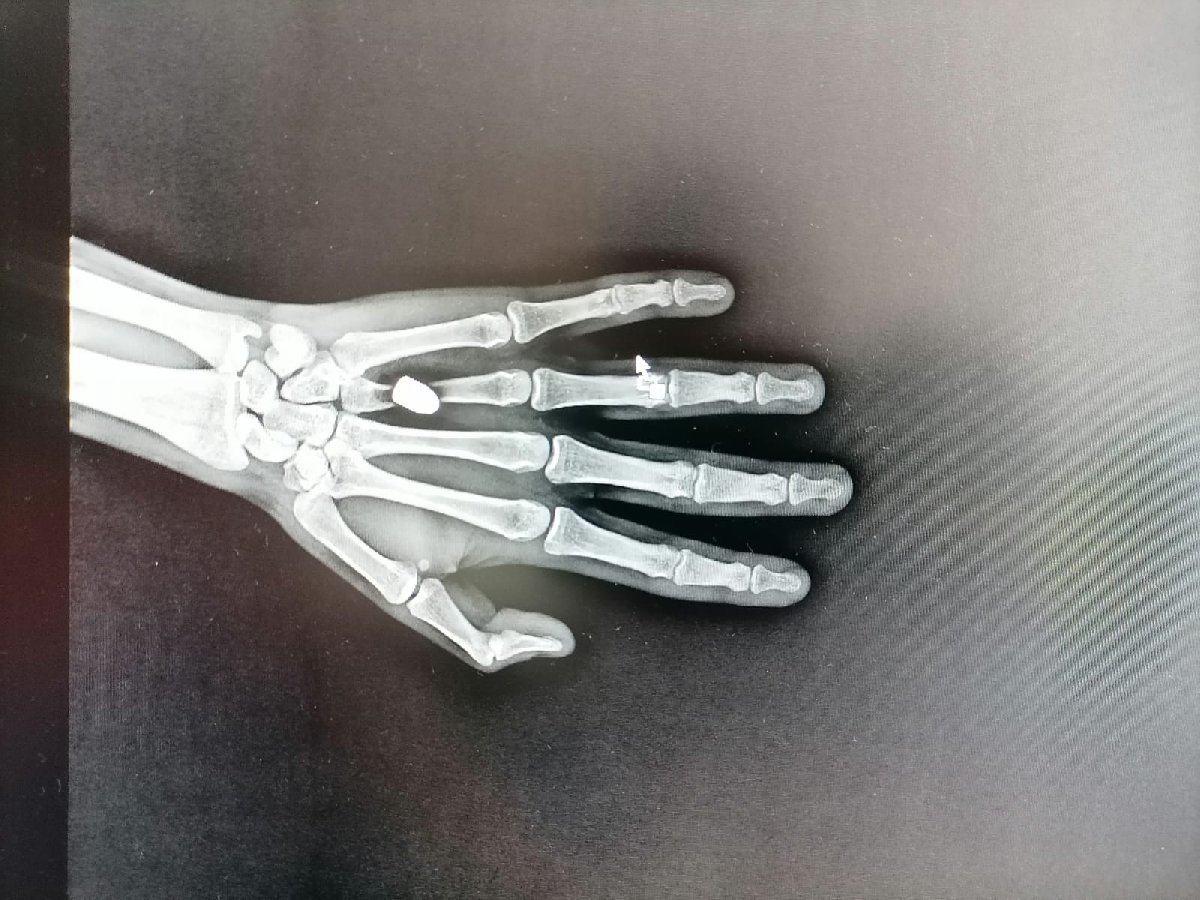

Özellikle Trabzonspor'un geçen sezon şampiyonluğu ve sonrasında alınan güvenlik önlemleri ile olumlu sonuç veren 'Mutluluğa kurşun sıkmayın' kampanyasından yaklaşık 5 ay sonra kentte ilk kez yorgun mermi vakası yaşandı. Sürmene ilçesi Çarşı Mahallesinde 22 Ağustos'ta otobüs durağında beklediği sırada elinde aniden acı hisseden Mehmet İskender, sol avucunun kanadığını fark etti. Kanı arkadaşının yardımıyla temizleyen İskender, Sürmene Devlet Hastanesi'ne gitti. Tedaviye alınan İskender'e çekilen röntgende, avucuna yorgun merminin saplandığı tespit edildi. Mermi çekirdeği elinden ameliyatla alınan İskender, taburcu edildi. Polis ekipleri, olayla ilgili inceleme başlattı.

DURUMU İYİ

Sürmene Devlet Hastanesi Başhekimi Osman Yoloğlu, röntgen filminde mermi tespit ettiklerini belirterek, "Elinde ağrı hissettiğini söyleyen hastamızın elinde de bir yarası vardı. Yaptığımız tetkikler sonrası elinde, mermi çekirdeği olduğunu tespit ettik. Hastamızı hemen ameliyata aldık ve elinden mermi çekirdeğini çıkarttık. Durumu, çok şükür iyi diye konuştu.